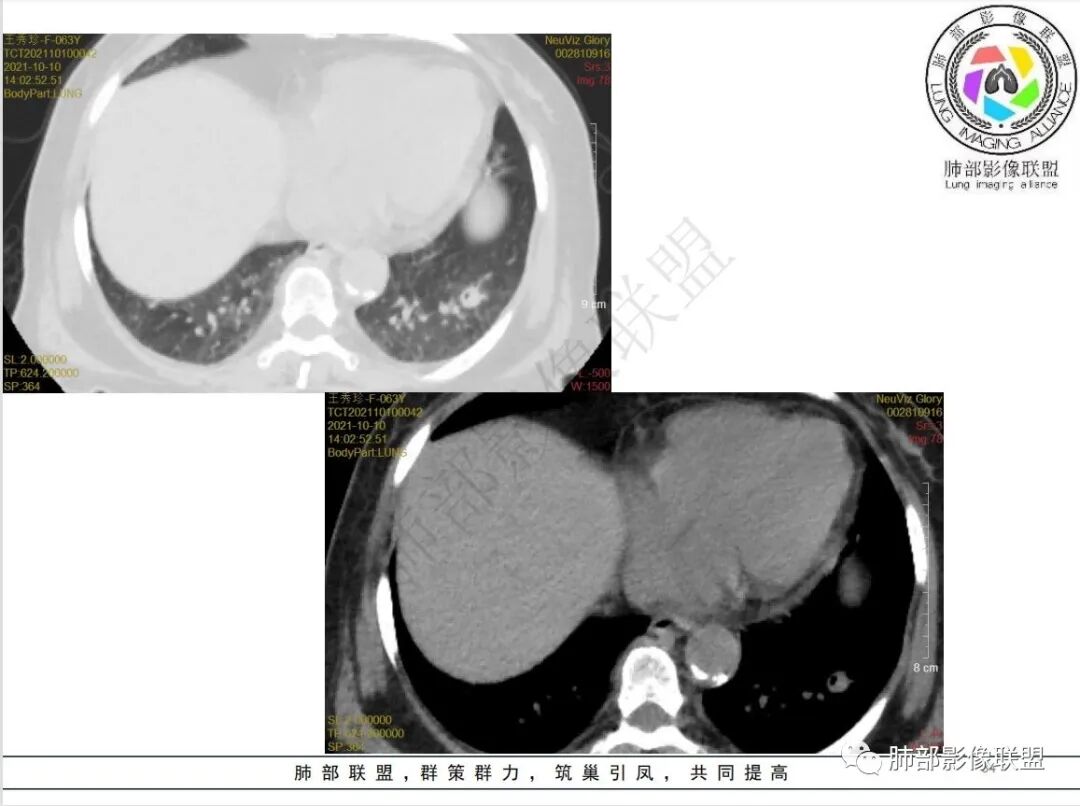

白血病病史,抗炎治疗后病灶明显增多,左肺有空洞并见液气平面,胸膜下楔形影,右肺有大片影,中心低外周密度高,符合血源性感染性病变,有位老师说过曲霉菌及结核属于干性坏死,不支持,毛霉和金葡都是液性坏死,本例有液气平面需要两者鉴别,从临床病史及影像进展情况看考虑支持毛霉菌感染,金葡一般进展比较快不支持,右肺动脉有侵犯,白血病肺侵润不知道有没有可能,工作中没遇到过,总之毛霉可能性较大,白血病肺浸润待排

老年女性,白血病史,粒细胞减少,肛周疼痛,高热,两肺多发结节,结节有晕征,治疗后肺内结节增多,并可见空洞,右肺门脓肿形成,右肺动脉受侵,纵隔内淋巴结肿大,白血病粒细胞减少常规思路,首先要考虑曲霉,曲霉在初诊治疗时,病变会增多,本例结节有晕,有血管侵蚀及胸膜楔形梗死灶,支持曲霉,有肛周疼痛,临床有发热,右肺门有脓肿,奴卡也要考虑

4.白血病化疗后,CT上出现多发结节,边缘可见晕征,病灶内可见多发坏死,右肺中叶肺动脉可见充盈缺损,右肺中叶可见融冰征,右肺中叶肺动脉侵犯栓塞伴右肺中叶肺梗死,可符合真菌感染。

6.肺曲霉病典型的CT表现是结节周围有磨玻璃样的晕征表现,或胸膜为宽基底的楔形实变。晕征表现为曲菌感染的肺结节伴梗死和凝固性坏死,周围有肺泡出血。最终可出现空泡征象,并可观察到中央坏死组织与周围肺实质分离形成空气新月征。